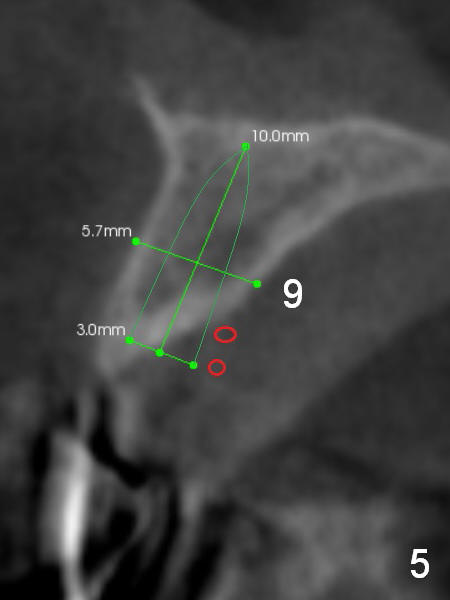

A 69-year-old man would consider implant option for his upper front teeth (Fig.1: #5-9) if there is no separate bone graft procedure. He does not want implants for his lower left molars (#18,19), since he has had a partial denture. In fact the bone at #5-9 is so thin that 2-3 mm 1-piece implants can be placed at #5,7 and 9 (Fig.2-5 (CT coronal sections (B: buccal)) for a 5-unit bridge (Fig.1). To support and increase the longevity of the latter, implants at #18,19 are mandatory (Fig.6,7).

Wheel saws will be used to split the ridge before drilling at #7 (Fig.4). Surgical bur is to be used for ridge reduction prior to osteotomy at #19 (Fig.6), while at #18, osteotomy depth will be 10 mm for 8 mm implant (Fig.7).